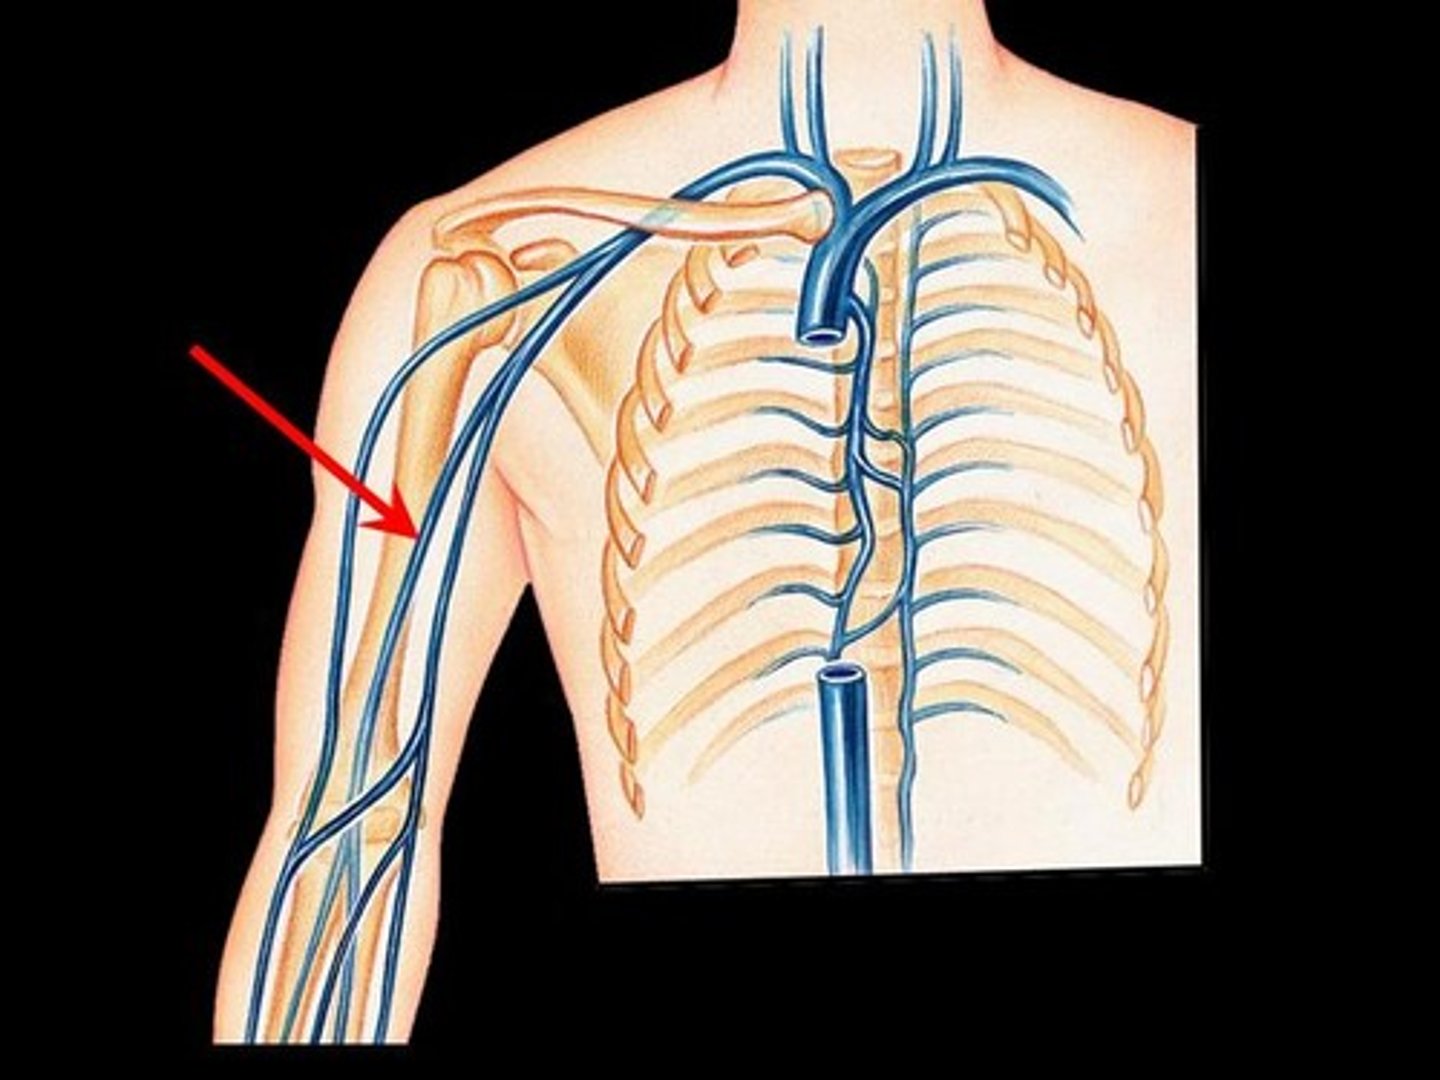

subclavian vein

axillary vein

brachial vein

cephalic vein